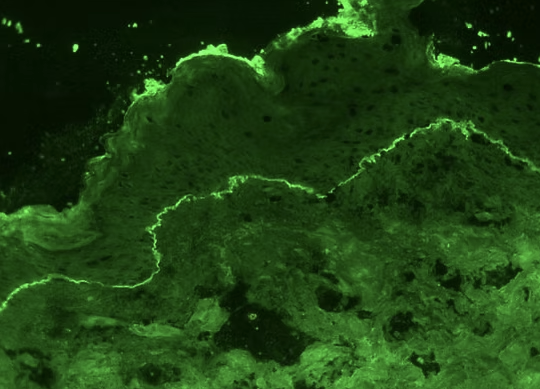

피부의 수포성 병변의 감별진단들

1. 천포창 (Pemphigus) 자가항체(IgG)가 데스모글레인(desmoglein, DSG) 에 결합하여 표피 및 점막상...